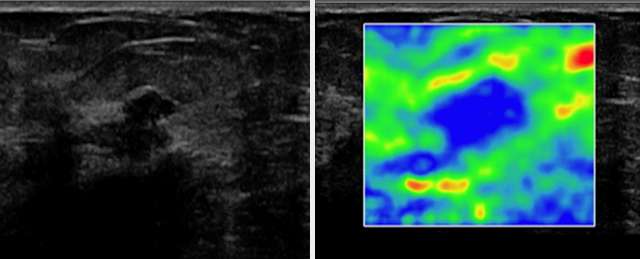

Another useful tool in conjunction with Doppler sonography is ultrasound elastography (sono-elastography), which uses sound waves to assess the mechanical properties of tissues (firmness). Soft lesions “deform” from sound waves more so than firm lesions. In general, malignant lesions tend to be firmer (deform less) than benign lesions. One application of this property is with Strain Elastography, where a color scale can be used to give a qualitative analysis of the firmness of a lesion. The two figures below, courtesy of the article “The Role of Sonoelastography in Breast Lesions” (Richard Barr, et. al), give an example of Strain elastography in evaluating a hypoechoic breast mass with irregular borders in a 63-year-old woman (left image). On elastography (right image), blue represents stiffer breast tissue and red, softer tissue. This lesion is blue, indicating a firm lesion, correctly increasing suspicion, as this lesion was biopsied and proven to be invasive ductal carcinoma.

Elastography and irregular borders